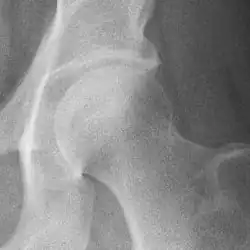

Hip

Hip joint with no signs of osteoarthritis.

The most commonly used radiographic classification system for osteoarthritis of the hip joint is the Kellgren–Lawrence system (or KL system).[6] It uses plain radiographs.